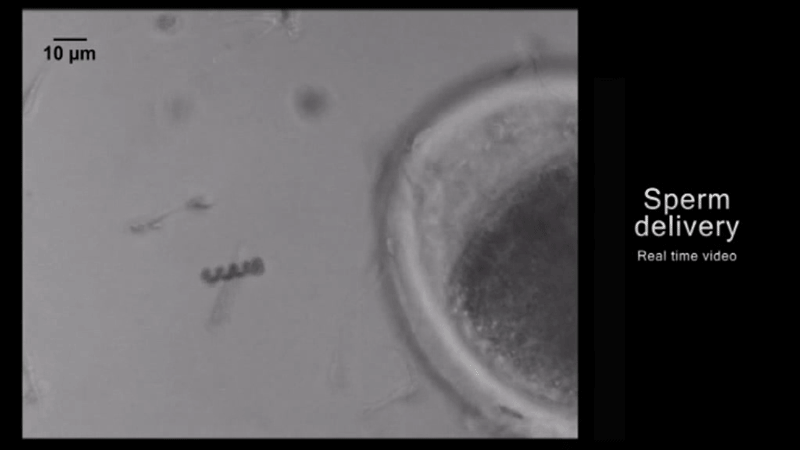

The researchers tested this by creating a “micromotor” that drives sperm, which they call a “cargo-delivery system,” to help treat gynaecological cancer – and tested it in a lab.

The mini structure they made consisted of four arms that released the drug-loaded sperm when it bends upon reaching the tumour. The structure is coated with iron, which was used to guide and release the sperm in the right place using an external magnet.

If this all sounds a bit heavy for the sperm cell, it is. The structure only traps the head, so the sperm’s tail is free to propel ahead, but the average velocity of the sperm-motor dropped by 43 per cent.

But in their tests, 15 out of 22 of the sperm/motor couples successfully release the sperm cells.